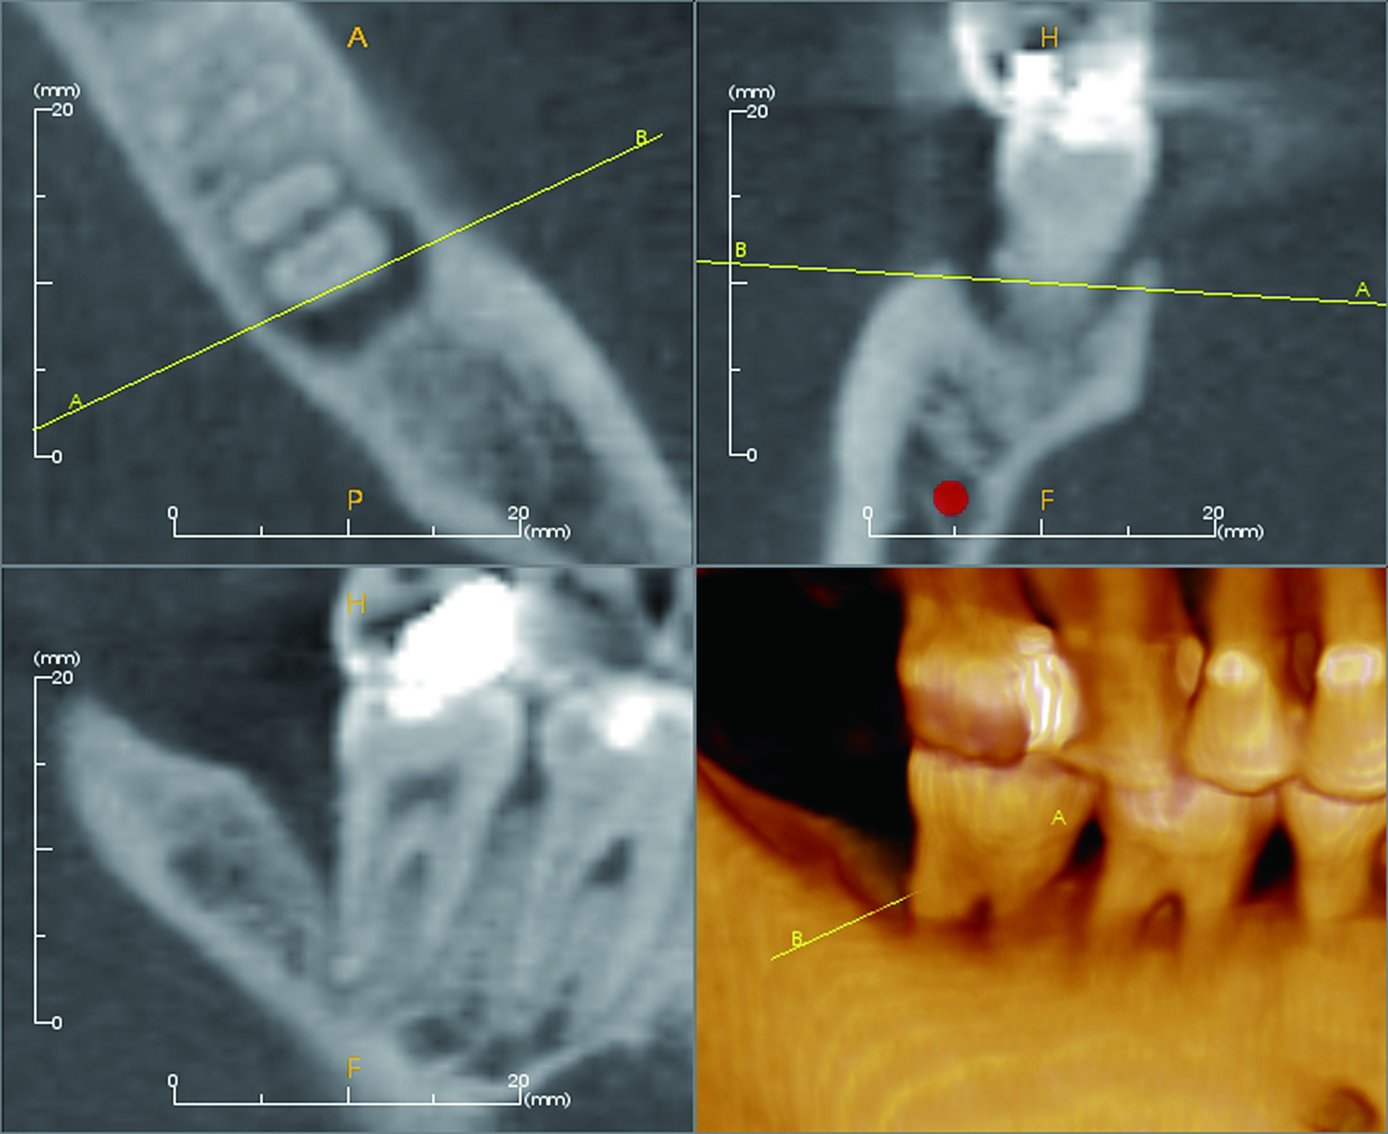

当院には正確で安全な治療を行うための検査機器をとして、最新鋭の歯科用CTシステムを導入しております。このシステムは、低い被ばく線量(総合病院などの医科用CTの1/10以下)で、3次元データの情報を得ることができ、これまでのレントゲン検査の診断が難しかった部分の診断も行えます。これにより患者さんのへのわかりやすい説明と更なる治療成績の向上が見込めます。